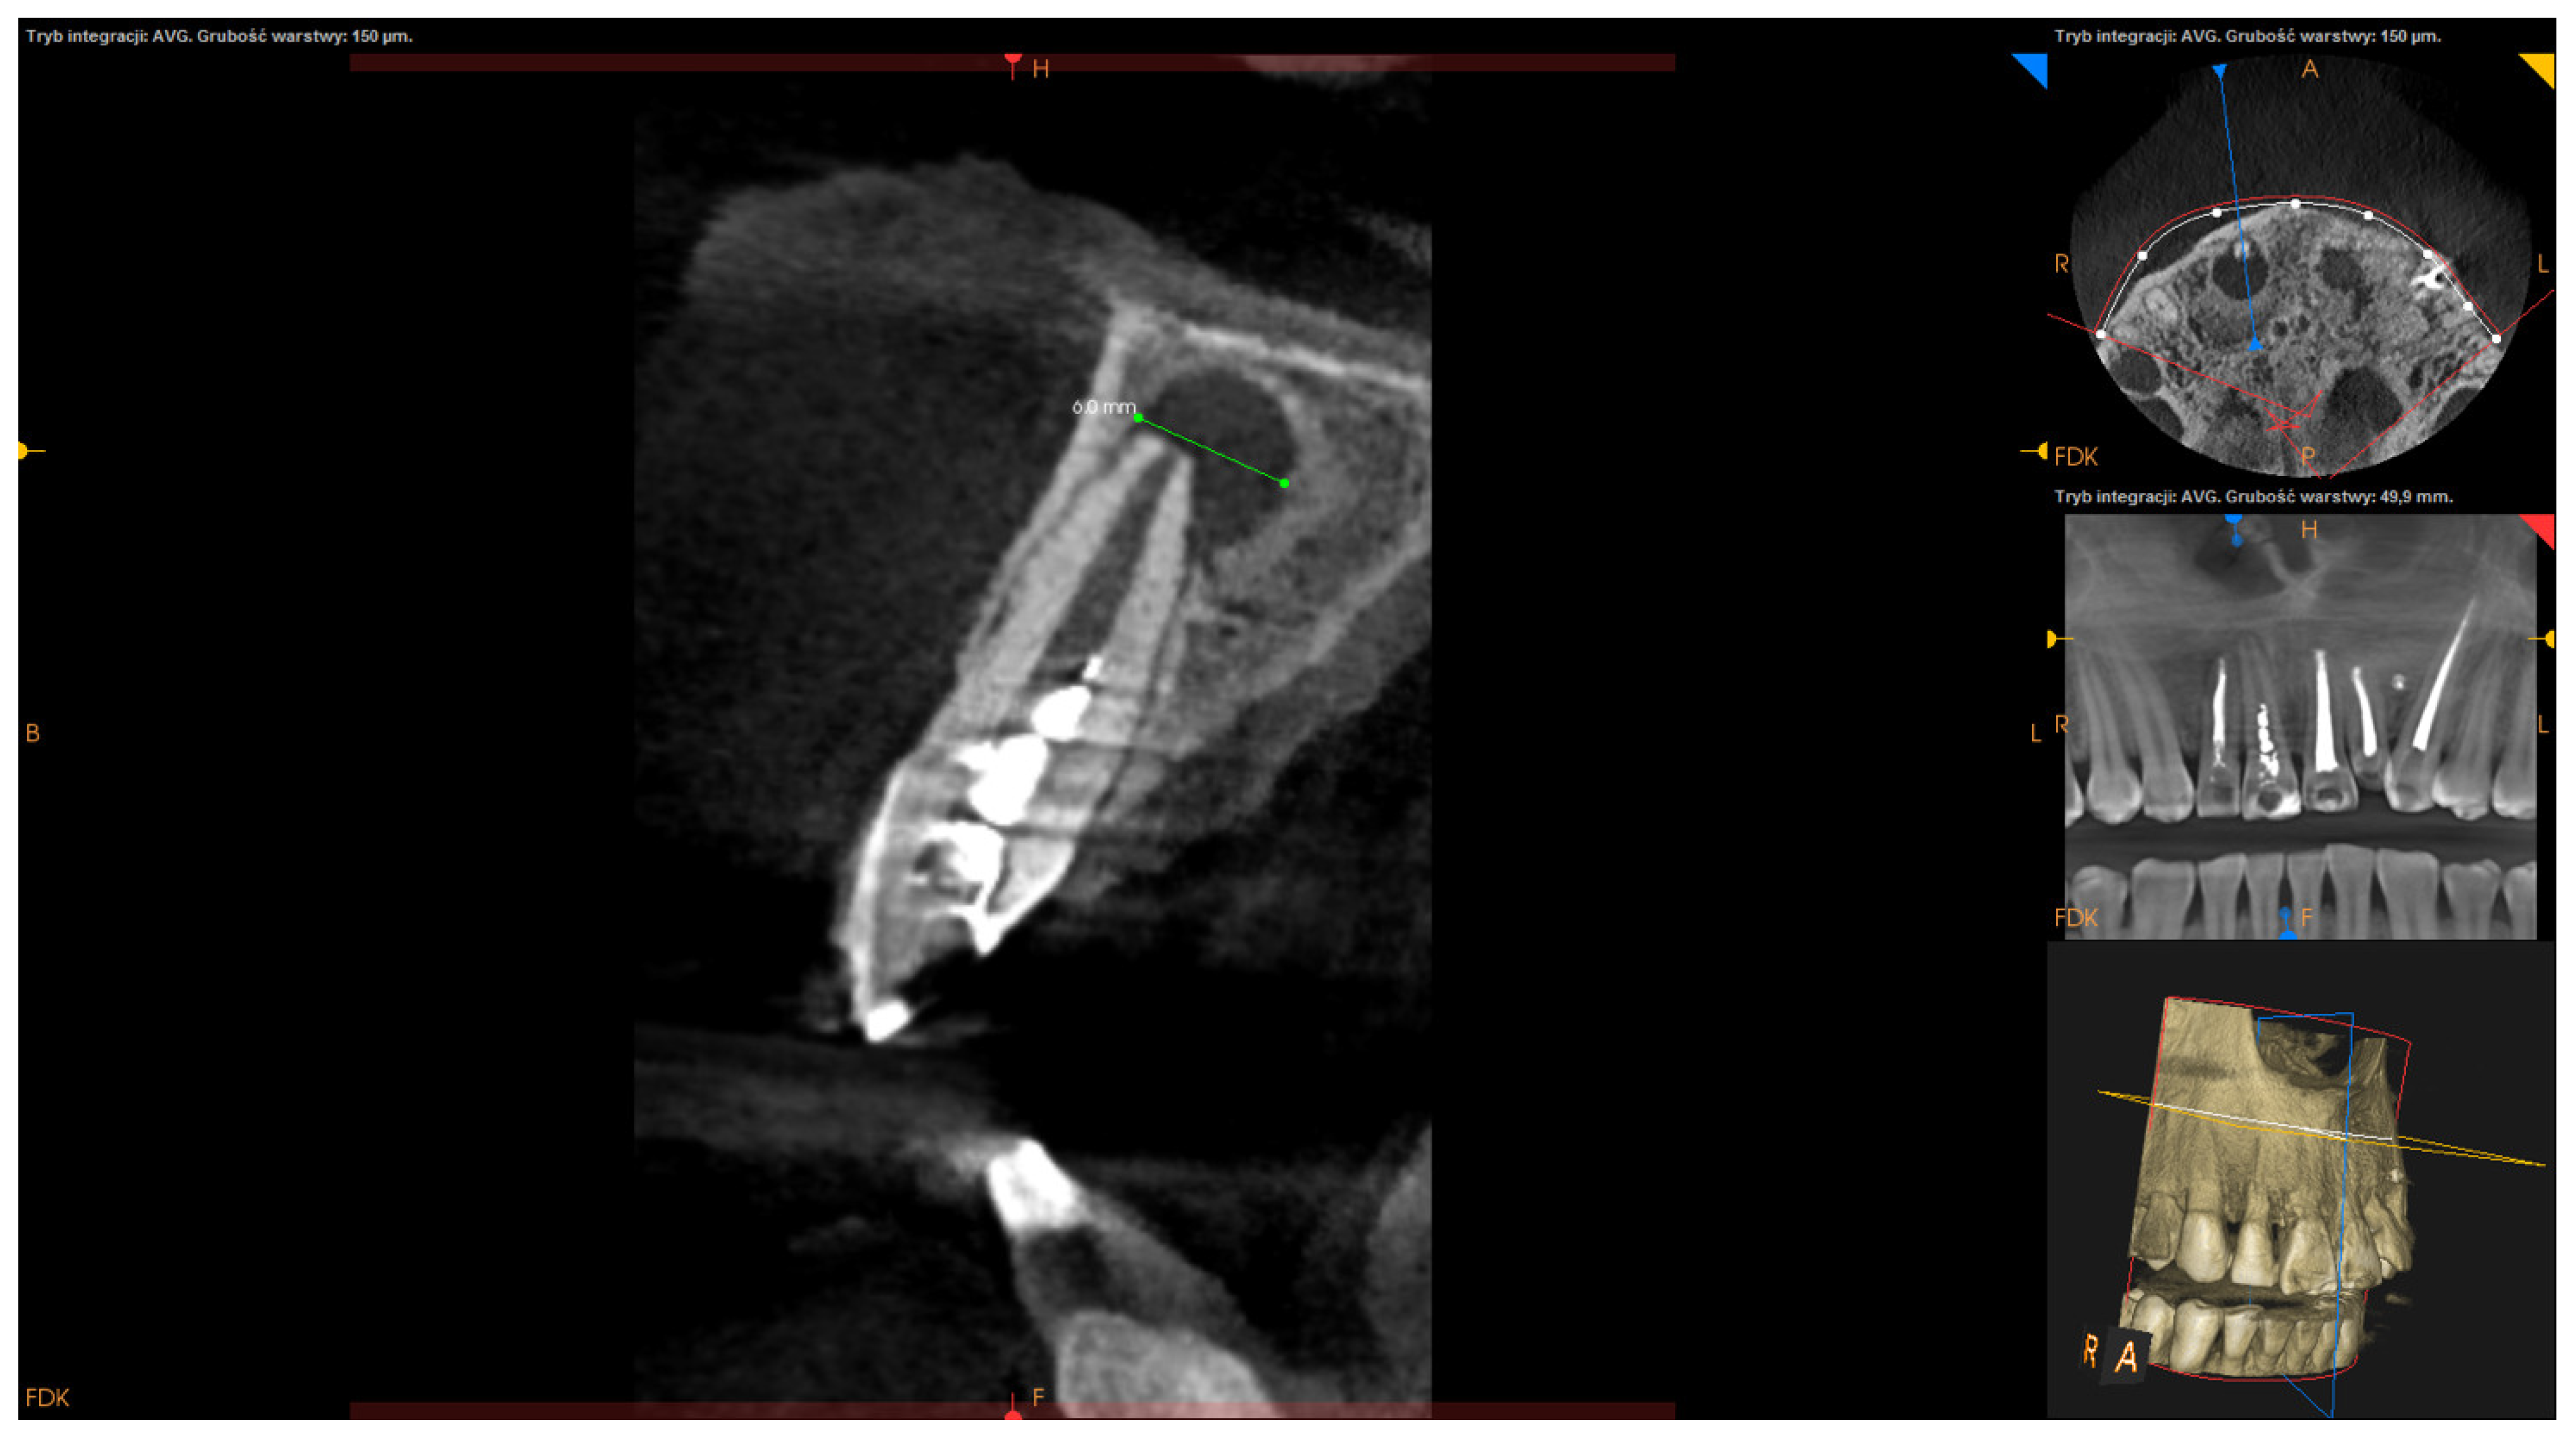

- Buccolingual maximum diameter (measured in the sagittal section) (Figure 3);

| buccolingual maximum diameter M ± SD: 6.91 ± 2.43 | <6.91 mm | 48 (53.93%) |

| >6.91 mm | 41 (46.07%) | |